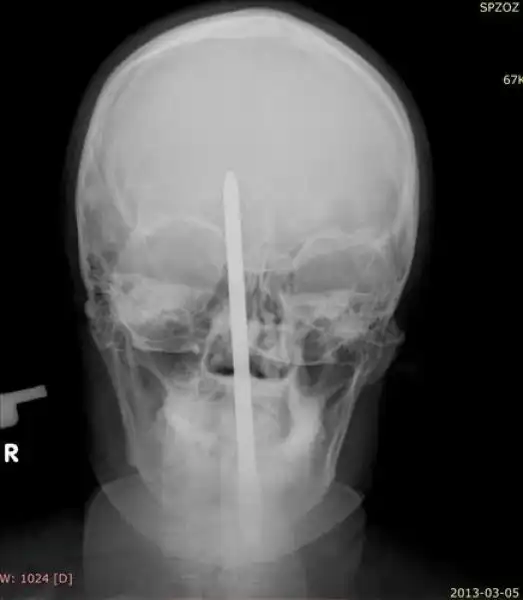

25-летний поляк трудился у себя в саду, когда потерял равновесие и упал на инструменты. Поднявшись и придя в себя он посмотрел в зеркало и обнаружил, что у него из головы торчит отвертка. Мужик не стал суетиться, а просто достал сигарету, закурил и отправился к соседу, чтобы тот помог ему добраться до больницы. Как оказалось, отвертка вошла в мозг на пять сантиметров, но очень удачно, поэтому инструмент без труда извлекли, а дырку залатали.